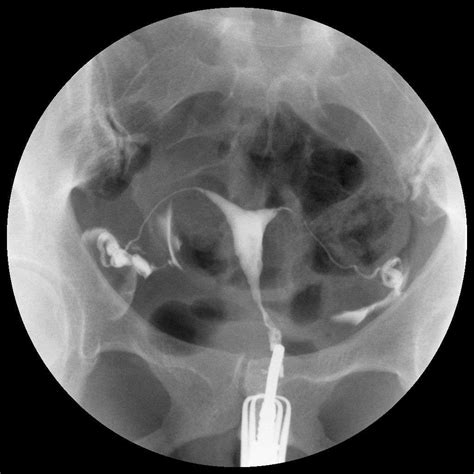

Diagnosticul obstrucției tubare se realizează printr-o serie de investigații imagistice, dintre care histerosalpingografia, ce implică utilizarea razelor X și a unui agent de contrast pentru vizualizarea trompelor uterine, reprezintă o metodă frecvent utilizată. Diagnosticul obstrucției tubare presupune o serie de investigații menite să evalueze starea și funcționalitatea trompelor uterine. Aceasta implică introducerea unei soluții saline sterile sau a unui agent de contrast în cavitatea uterină, permițând vizualizarea detaliată a structurii și formei acesteia. În contextul infertilității, sonohisterografia poate fi completată de sonohisterosalpingografie, o metodă care evaluează permeabilitatea trompelor uterine prin injectarea unui colorant și monitorizarea fluxului acestuia cu ajutorul razelor X. Trompele uterine înfundate pot fi dificil de detectat. histerosalpingografia (HSG): în timpul acestei proceduri radiologice, medicul injectează o substanță de contrast în uter, substanță care se deplasează apoi către trompele uterine. Acest lichid inofensiv este vizibil pe radiografie. O altă metodă de diagnostic, laparoscopia exploratorie, oferă cele mai precise informații despre starea trompelor uterine, însă din cauza caracterului său invaziv, nu este întotdeauna recomandată ca primă opțiune. La SANADOR, investigațiile moderne asigură diagnosticarea precisă. La SANADOR beneficiezi de analizele și investigațiile necesare pentru un diagnostic rapid și corect. SANADOR dispune de tehnologie medicală de ultimă generație, pentru diagnostic avansat și tratament eficient. La SANADOR, pacientele beneficiază de evaluare medicală completă pentru afecțiuni ginecologice, realizată prin consult de specialitate și investigații minuțioase, în funcție de indicație.